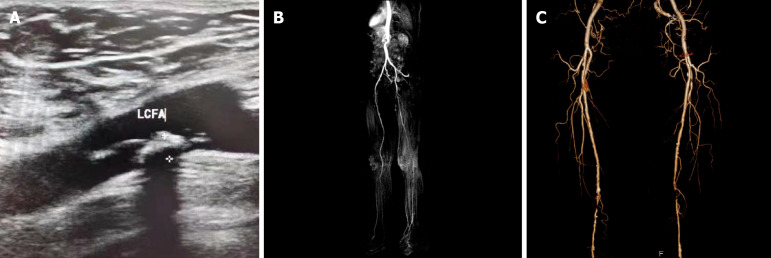

Aim: To investigate the effectiveness of the combination of doppler ultrasonography (DUS), three-dimensional dynamic contrast-enhanced magnetic resonance angiography (CE-MRA), and CT angiography (CTA) in assessing lower extremity arterial disease in diabetes mellitus (DM).

Methods: This study retrospectively analyzed the imaging and clinical data of 116 patients diagnosed with DM complicated with lower extremity vascular diseases from January 2021 to June 2023. All patients underwent unilateral or bilateral DUS, CTA, and CE-MRA as well as invasive digital subtraction angiography (DSA). The application values of DUS, CE-MRA, and CTA were compared.

Results: A total of 152 lower extremity arteries in the 116 patients were graded following the classification of vascular branches. The Kappa values between DUS and DSA were 0.780, 0.755, and 0.806 for diagnosing moderate stenosis and 0.484, 0.699, and 0.449 for severe stenosis of grade 1 arteries, grade 2 arteries, and grade 3 arteries, respectively. The Kappa values between CE-MRA and DSA were 0.784, 0.814, and 0.835 for diagnosing moderate stenosis and 0.694, 0.748, and 0.606 for severe stenosis of grade 1 arteries, grade 2 arteries, and grade 3 arteries, respectively. The Kappa values between CTA and DSA were 0.900, 0.858, and 0.878 for diagnosing moderate stenosis and 0.882, 0.823, and 0.756 for severe stenosis of grade 1 arteries, grade 2 arteries, and grade 3 arteries, respectively.

Conclusion: DUS, CE-MRA, and CTA demonstrated comparable accuracy in diagnosing lower extremity arterial disease in DM, and the consistency between CTA and DSA diagnoses was higher than the other two imaging methods.